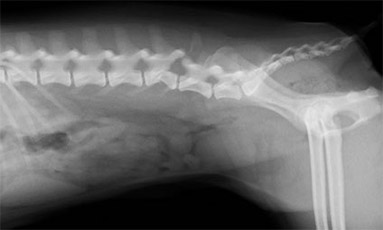

腰椎椎体骨折

-

手術前

手術後

柴犬の飛び出しによる交通事故により発生しました。プレートによる椎体固定を行い、経過良好です。